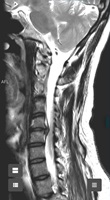

En C5-C6 cambios degenerativos con complejo disco osteofitario que condiciona estenosis moderada del canal raquídeo cervical, apreciando signos de mielopatía compresiva. Estenosis foraminal bilateral moderada en C5-C6 e izquierda leve en C6-C7 |